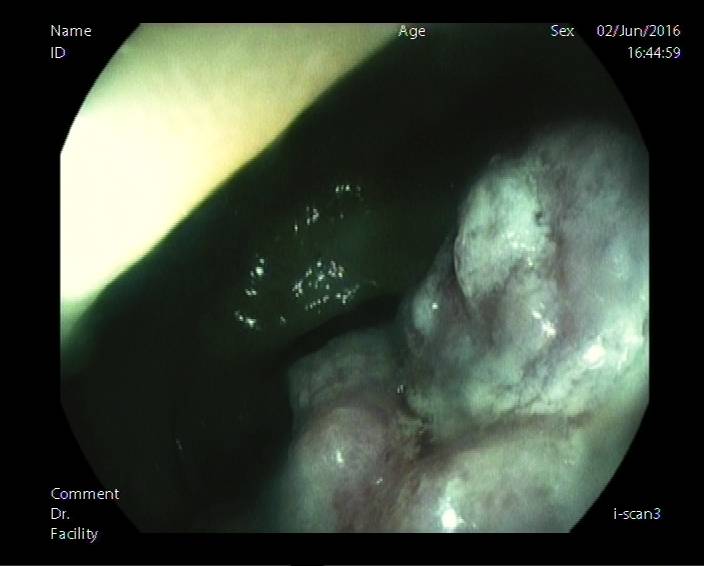

图7a:距肛门12cm可见带蒂息肉,直径约1.5cm。用水清洗病灶表面去除黏液。首先我们可以肯定的是表面存在pit。放大2倍观察,初步认为病灶表面pit(白色线状)成脑回状或树枝分叉。此时需与V1型pit相鉴别。V1型pit极度不规则,大小不等,形状不一(可参考图4f)。故认为IV型pit可能性大。

图7b:此图左侧可见息肉蒂表面pit,呈类圆形,由于无法放大观察,I型与II型pit无法鉴别(星芒状pit非放大情况下仍可能为类圆形),但至少可以判定为非腺瘤性病变。另:笔者并未使用zoom放大功能,此图为浸水后观察病灶,仍能清楚的观察到病灶表面的pit(放在水中的筷子会变大)。

病理回示:(直肠)腺瘤性息肉,小灶呈中-重度不典型增生。